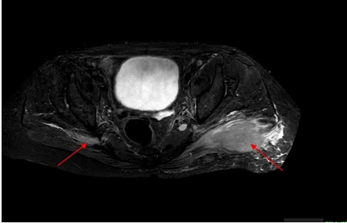

Figure 1b A soft tissue lesion measuring (AP *ML * SI) 19 x 25 x25mm is seen in right Gluteus Medius muscle (on MRI STIR axial images).

MRI Gluteal region PD SPAIR PDW SPAIR (Proton Density Weighted Spectral Attenuated Inversion Recovery), a) Coronal images b) axial images showing large hyperintense soft tissue lesion in left gluteus maximus muscle (red arrow) with surrounding edema and lesion seen on right side in gluteus medius muscle.